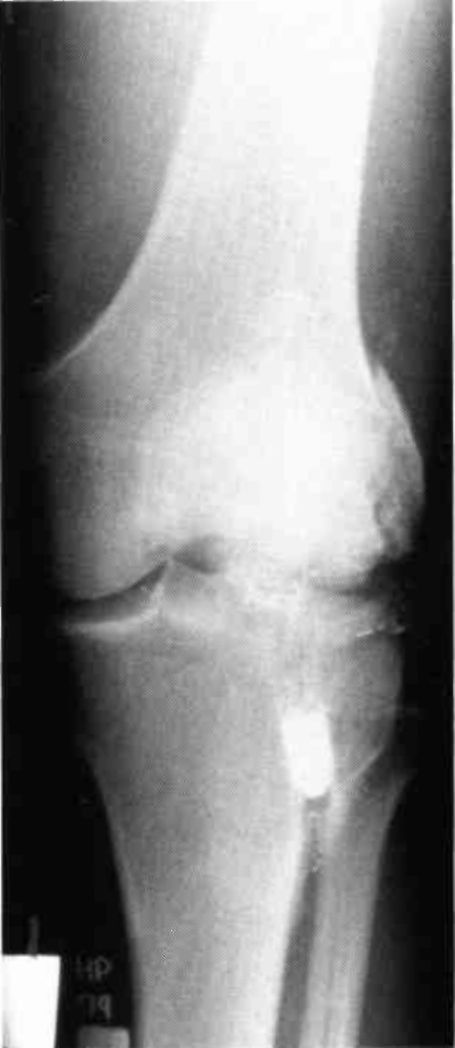

A nineteen year old male sustained a distal fracture with a split condylar fracture to the right leg (Fig. 10) and a lateral condyle fracture on the contralateral side (Fig. 11). Fractures were stabilized, but were not internally fixed at time of admission because of emergency vascular repairs being required. Three days post injury, the patient underwent ORIF of his fractures (Fig. 12 and Fig. 13). The right leg was placed in a free knee Mobilizing Brace and the left leg was placed in the rehabilitative free knee orthosis. A continuous passive motion dynamic suspension system was placed on the lower right extremity (Fig. 14). The lower left extremity had normal pain free motion following surgery. The patient was kept in passive motion for five days and achieved 0-100° of pain free motion. A cast brace was applied on the right extremity; the patient received gait training and was discharged.

Figure 10:

Figure 11: